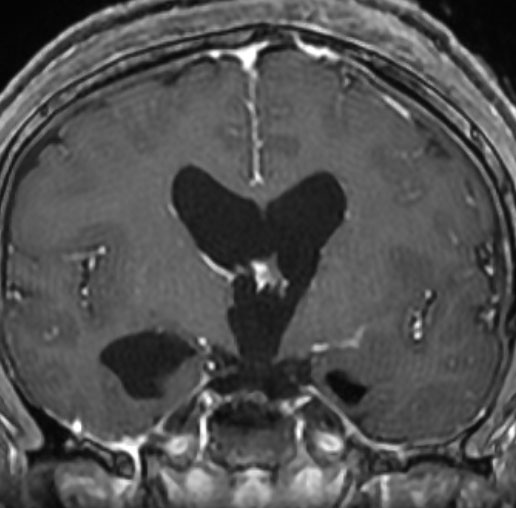

CTでは壁が厚く高密度,MRI T2強調画像では低信号,T1強調画像では高信号です。内部に血液を含んでいるようなのう胞に見えます。のう胞の壁は非常に厚く硬いものが予想されます。閉塞性水頭症になっています。

若い男性ですが,内視鏡手術では摘出できない壁がガチガチのものでした。モンロー孔が広いので経脳梁到達法 transcallsal approachで手術しました。右前頭部から入ろうとしましたが,架橋静脈のために入れず,左前頭葉を除けて,透明中隔の正中に達しました。ところが,左の脳弓が菲薄化して広がり腫瘍の上面にみえましたから,左のモンロー孔からは摘出できませんでした。しかたがないので,右のモンロー孔から腫瘍を摘出しています。腫瘍の周囲には第3脳室脈絡叢が広範囲に癒着していました。のう胞内容は暗褐色の古い血腫でした。のう胞の壁は硬く厚い結合織で肉芽腫のような肉眼所見でした。左右の脳弓にも癒着し,内大脳静脈にも癒着していたので,その部分には皮膜を残しました。

術後のMRIです。幸い,記憶障害などの脳弓症状はでませんでしたが,かなりリスクの高い手術でした。